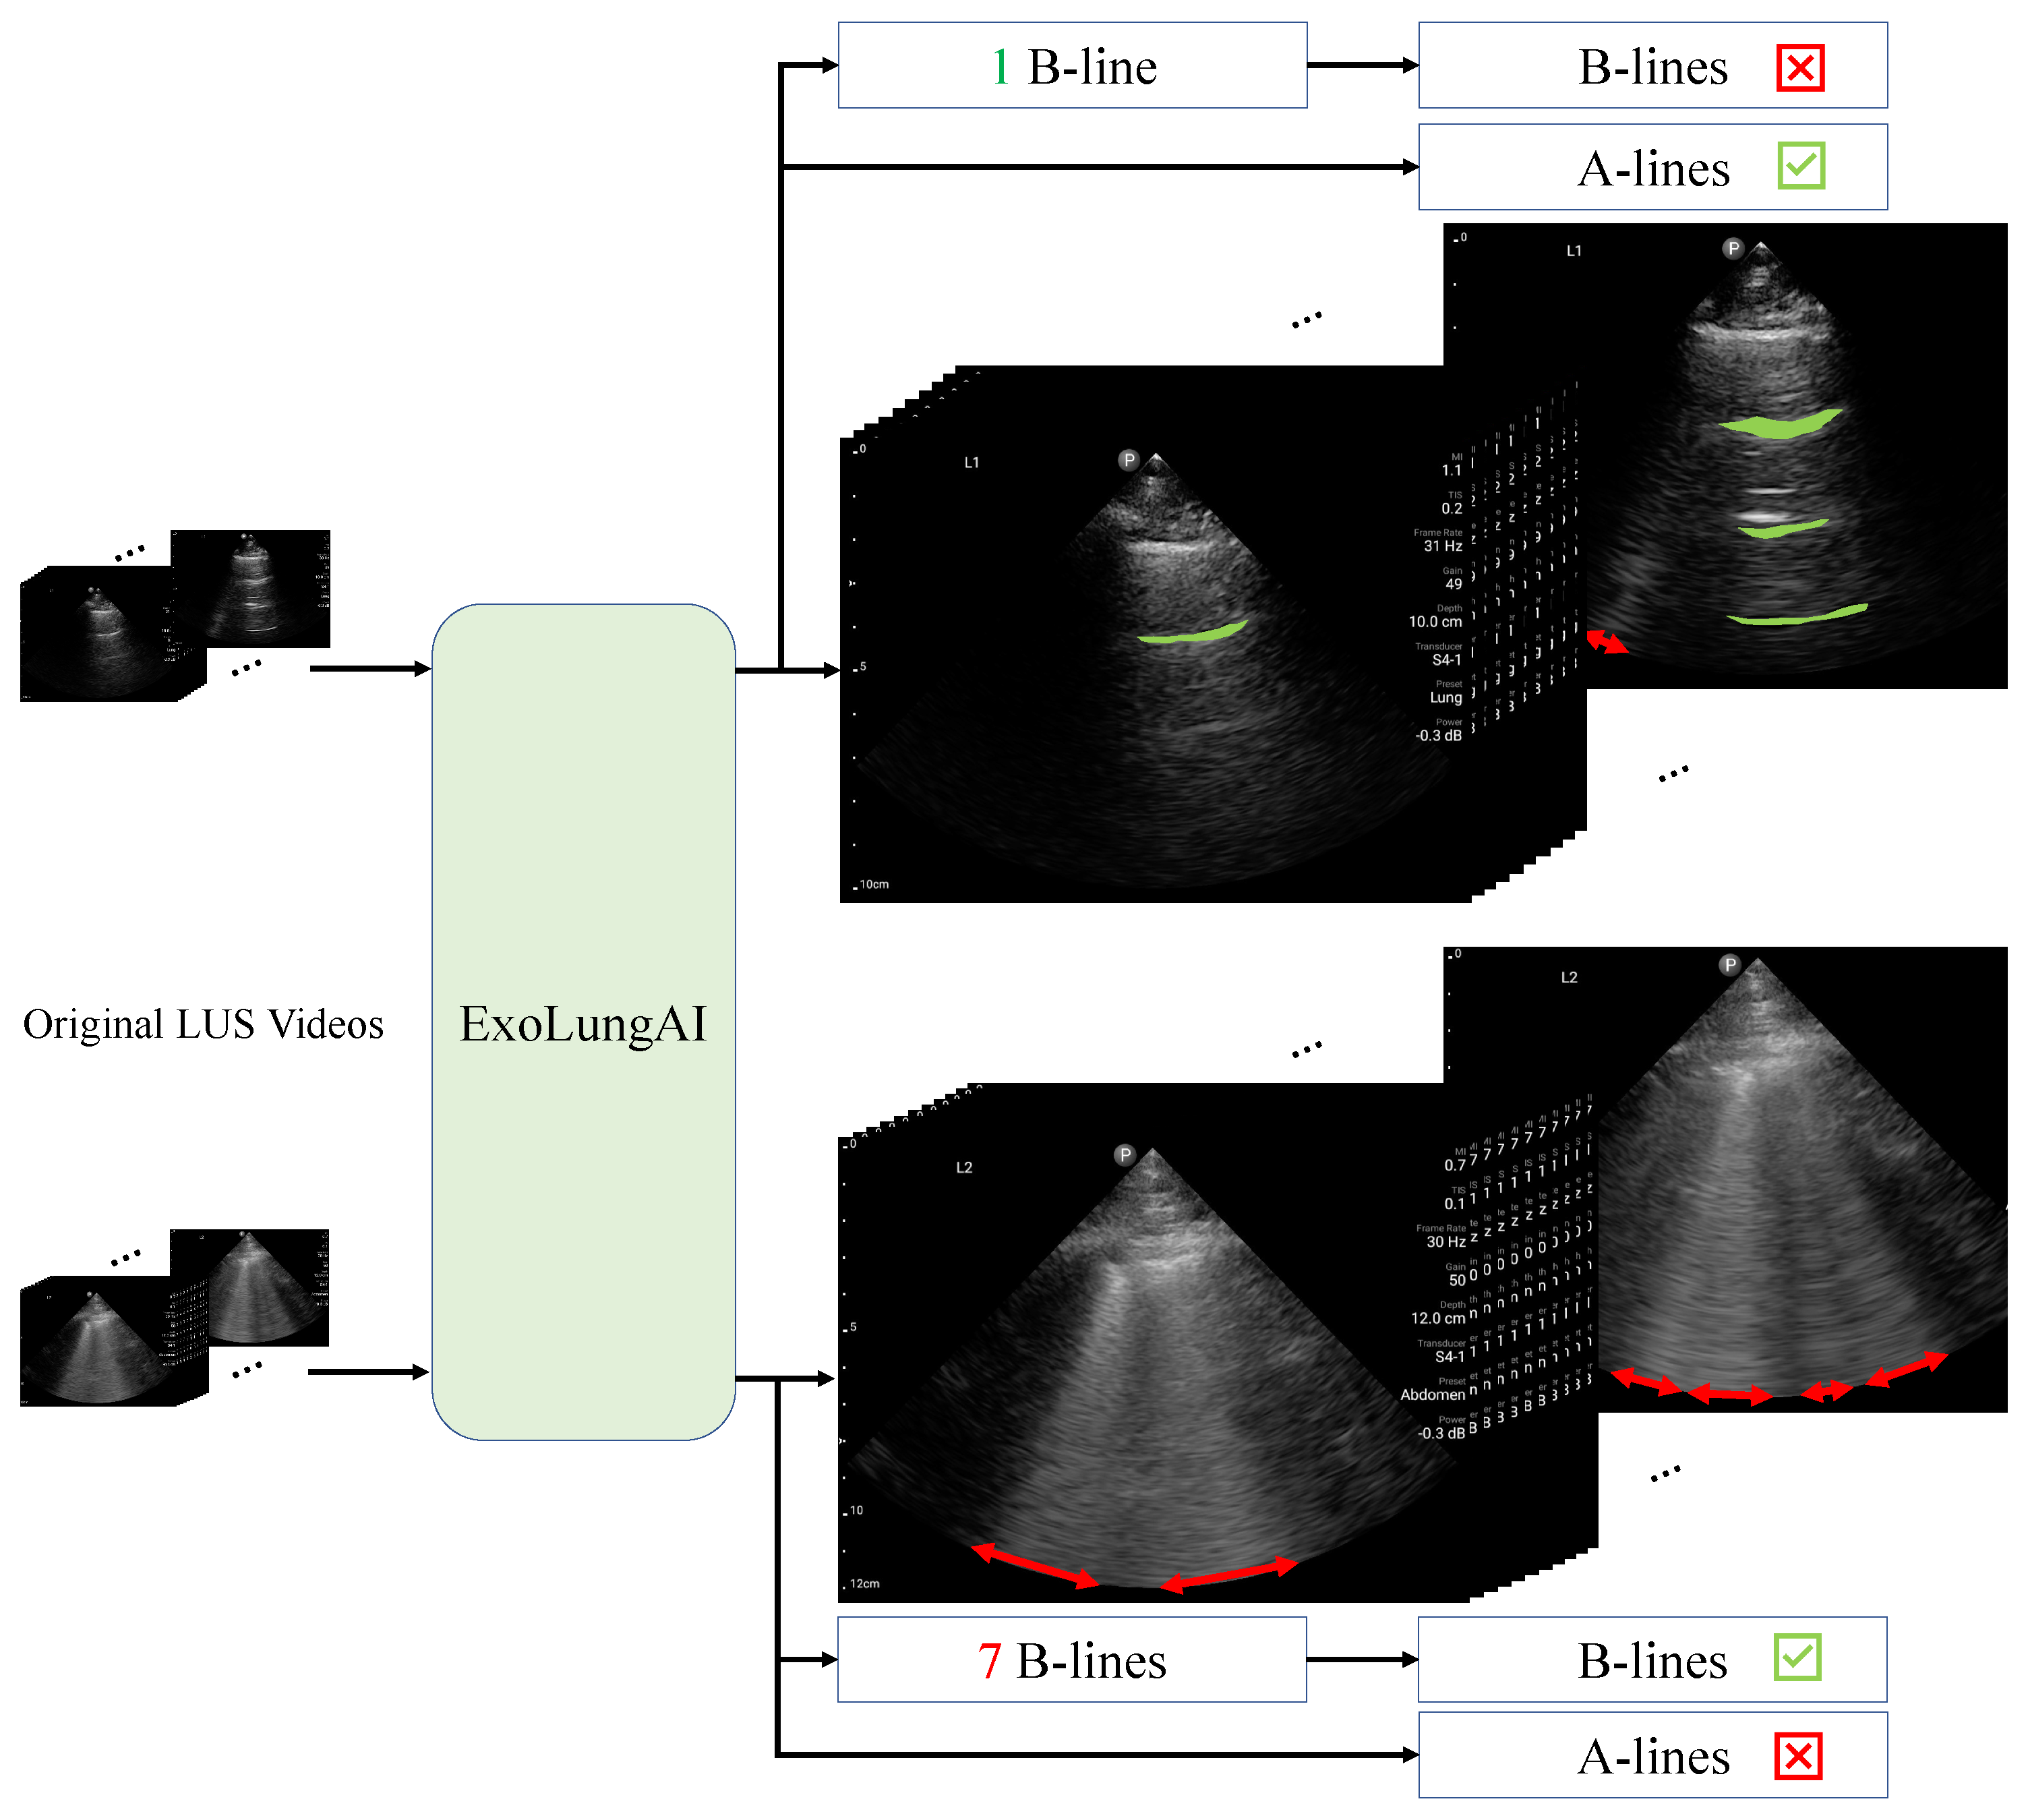

Enhancing Lung Ultrasound Diagnostics: A Clinical Study on an Artificial Intelligence Tool for the Detection and Quantification of A-Lines and B-Lines

2.2. Approach